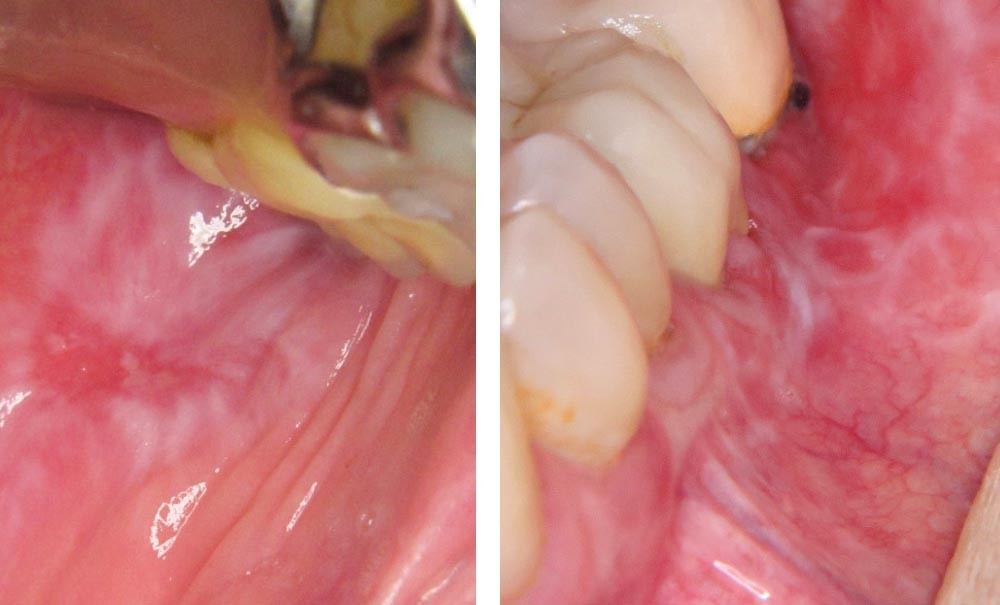

On observait une large plage érythémateuse et kératosique sur la joue gauche. En périphérie, la kératose avait un aspect dendritique. Au centre de la lésion kératosique, siégeait une ulcération.

Une biopsie de la plage kératosique à proximité de l’ulcération a été réalisée. Elle a confirmé le caractère lichénoïde de la lésion avec présence d’un épithélium orthokératinisé au sein duquel siégeaient quelques corps apoptotiques. Au sein du chorion, il existait un infiltrat lymphoplasmocytaire lichénoïde. Aucun signe de malignité n’était visible sur l’échantillon analysé.